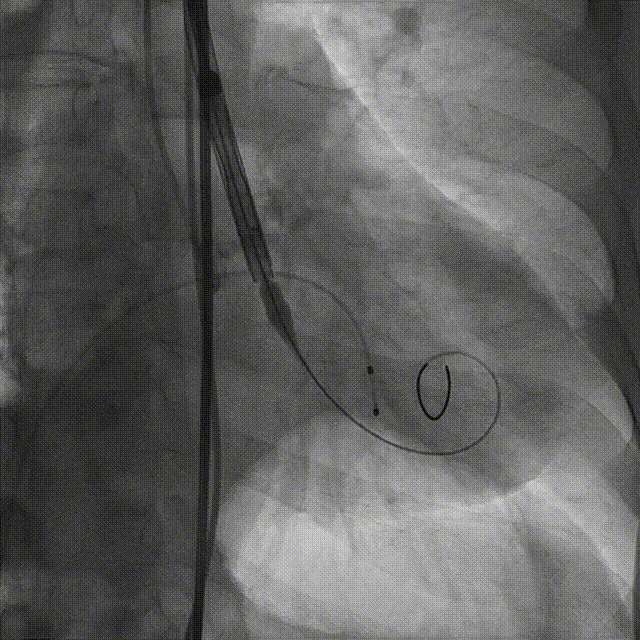

3.20mm球囊预扩,轻微腰征,冠脉显影良好,无造影剂渗漏

20mm球囊预扩